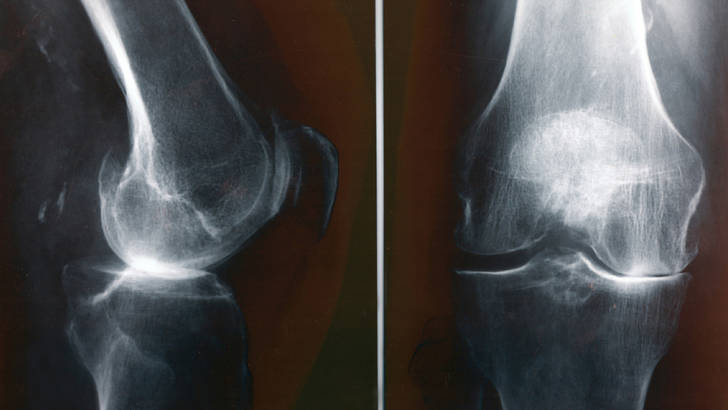

• arthrose

Notre corps peut régénérer ses cartilages de la même manière qu’il peut cicatriser une plaie, même si cela peut prendre plus de temps. Bien sûr, tout dépend de nombreux paramètres, comme l’âge, le stade d’usure cartilagineuse, le régime alimentaire ou les prédispositions de chacun. Chez certaines personnes, la régénération sera impossible.